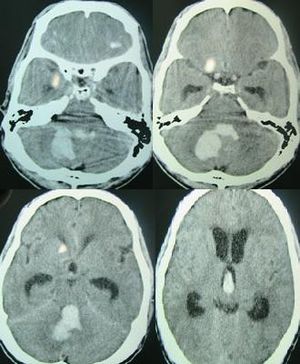

CT scan showing hemorrhage in the posterior fossa[1]

Spontaneous ICH with hydrocephalus on CT scan[1]

يتم التعرف على النزف الدماغي عن طريق التصوير المقطعي المحوسب حيث تظهر الدماء أكثر أفتح عن الأنسجة ويفصلها عن الجدار الداخلي للجمجمة نسيج الدماغ. الأنسجة المحيطة بالدماء عادة ما تكون أقل كثافة عن بقية الدماغ بسبب الوذمة، ومن ثم فيظهر أفتح في التصوير المطقعي المحوسب.